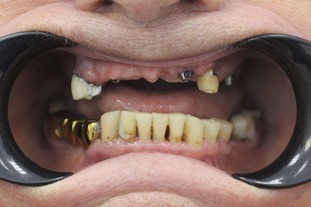

До

После

Неравномерная патологическая стираемость зубов. Установлены импланты в боковых отделах верху и внизу. Протезирование на имплантах циркониевыми коронками+ виниры на передние зубы.